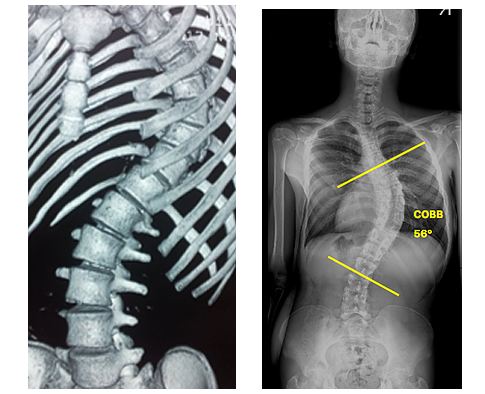

Другие причины боли в районе левой лопатки – остеохондроз, сколиоз, кифоз, спондилоартроз, радикулит, грыжа или опухоль позвоночника, межреберная невралгия.

Искривление позвоночника может начаться при плохом тонусе мышц

Другие причины возникновения боли в правой лопатке с иррадиацией в верхнюю конечность и плечевой пояс:

- сколиоз и кифоз;